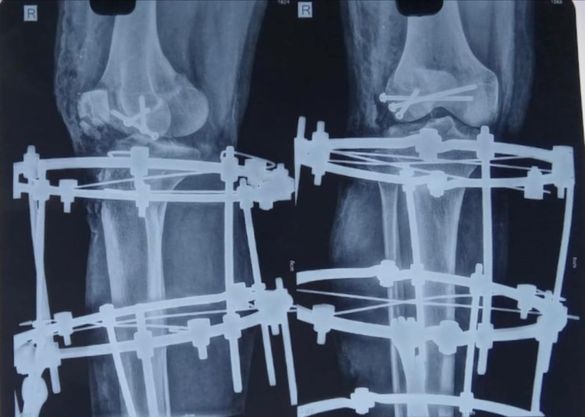

68 year old man ACL (anterior cruciate ligament) reconstruction of Knee

There used to be a common consensus that ACL reconstruction of knee should not be done in old age, this idea has now largely been debunked with statistical evidence. this 68 year old man with a traumatic anterior cruciate ligament tear had intact lateral and medial meniscus and quite normal cartilage in the weight bearing […]